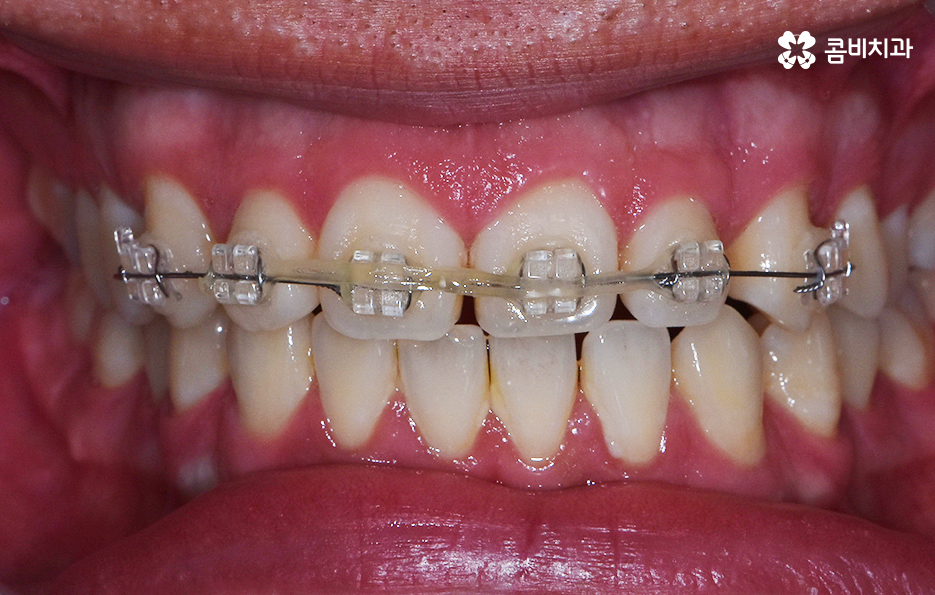

위 사례의 경우 앞니만 치아부분교정 통해서 치료가

이뤄진 사례로 치아의 돌출 여부나 골격, 교합 등을

고려하여 큰 문제 없이 치료가 가능했던 사례입니다.

위 사례의 경우 유독 앞니 위주로 치아가 벌어져 있는 상태이며

옆모습의 경우에도 비교적 양호한 상태입니다.

치아부분교정은 위 사례와 같이 대부분 앞니 6개의 치아에

부분적으로 교정 장치를 부착하여 진행이 되며